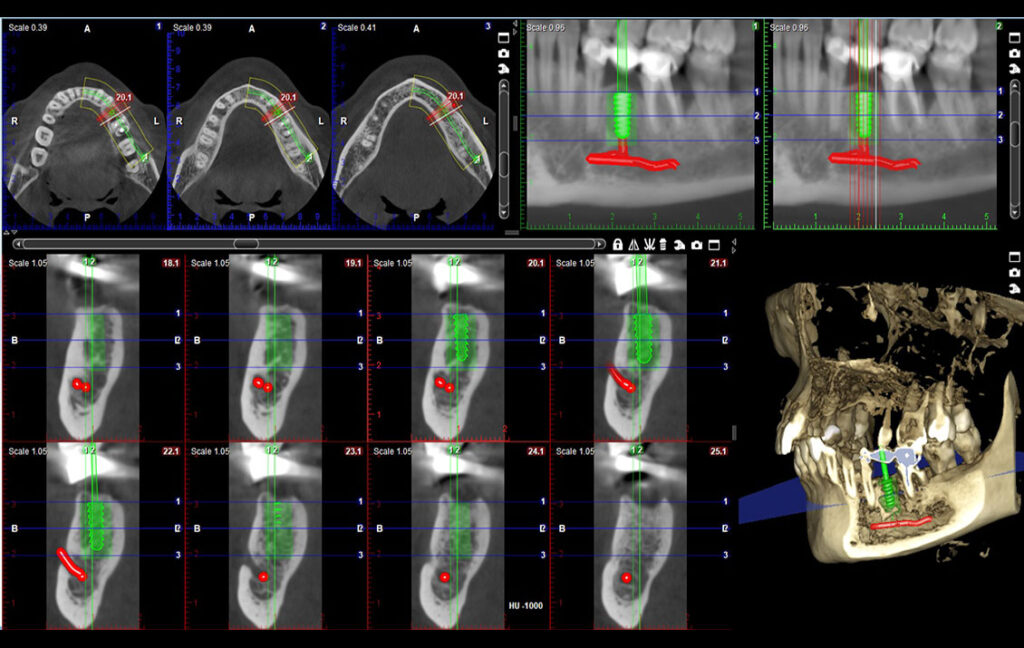

06. Implant plan

07. Alatka za formiranje regije

Primena CBCT snimka u oblasti:

Maksilofacijalna Hirurgija

Oralna Hirurgija

Implantologija

Dentalni program

Veličina polja

Veličina voksela, izotropni

Zubi

Ø80 x 50 mm

Ø80 x 80 mm

Ø100 x 60 mm

Ø100 x 100 mm

Ø68 x 42 mm

Ø68 x 68 mm

Ø85 x 50 mm

Ø85 x 85 mm

150 µm, 200 µm, 400 µm